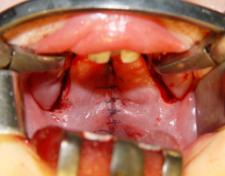

For illustration we present the stages of complex

treatment of the S.Yu-va patient (Fig. 6), who came to the clinic at 3 months

of age. After third degree determination of the intermaxillary bone the presurgical

patient preparation was carried out by using of the innovative technologies

(non-removable supramaxillary orthodontic device, fixed by microimplants). Bilateral

cheiloplasty was made at the age of 6 months and sparing palatoplasty-at the

age of 1.5 years.

À Á

Ã

Ä Å

Æ Ç

È

Fig. 6 - Patient S.Yu-va, 3 months.,

diagnosis: Congenital bilateral cleft lip and palate (3 degree of the intermaxillary bone deformation):

À) Patient`s appearance when

delivered to the hospital,

B)

Plaster cast of the frgaments of the upper jaw before treatment,

C)

The fitting of supramaxillary orthopaedic device on the plaster cast,

D) The fixation of supramaxillary orthopaedic device by microimplants to the jaw

fragments,

E) Intermaxillary bone status in patient at the age of 6 months,

F)

The patient state after bilateral cheiloplasty,

G) Palate tissues status in patient

at the age of 1,5 month before surgery,

I) Palate tissues status in patient

at the age of 1,5 month after palatoplasty,

J) Patient`s appearance S. Yu-va at

the age of 2 years.